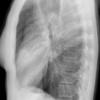

Case 2  Lingular pneum Lat

Date: 04/17/2005

Views: 6965